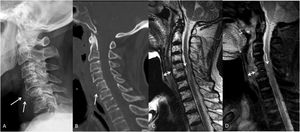

Patient received treatment with antibiotics and a Philadelphia collar after his admission. Ten days later, without clinical improvement of shoulder abduction we consider the need for a surgical debridement. Surgical treatment for spondylodiscitis is usually performed through an anterior approach that involves debridement, vertebral body curettage or resection and anterior fixation and fusion. However, in the reported patient, after careful evaluation of the serious soft tissue-damaged state of the anterior neck, the option of doing an anterior approach was discarded. The option of a conservative management with a cervical collar was discarded due to the risk of progressive neurological deterioration. The patient was treated with a posterior approach and fixation by bilateral facet joints C4-C6 and pedicle C7 screws without debridement, associated with 8 weeks of antibiotics. A nasogastric tube was placed in the esophagus for parenteral nutrition during this period although the dilaceration caused by the dilation was probably closed spontaneously. The patient showed progressive improvement, regaining strength in the upper limb (M: 4/5). A 6-month control MRI showed resolution of C5/C6 osteomyelitis and no evidence of abscesses or sinus tracts, although it showed intramedullary expansive high signal (C4-T11), anterior medullary synechiae, and persistent dural and arachnoid enhancement throughout the cord (Fig. 2). After 6 months, total strength was regained without signs of infectious processes after an 8-year follow-up.

A. Lateral cervical radiograph at six months post-operation: posterior fixation with bilateral facet screws at C4-C5-C6 and pedicle screws at C7 six months after surgery; B. MRI at 6 moths post- operation showed resolution of C5/C6 osteomyelitis and no evidence of abscesses or sinus tracts, although it showed intramedullary expansive high signal (C4-T11), anterior medullary synechiae, and persistent dural and arachnoid enhancement throughout the cord.